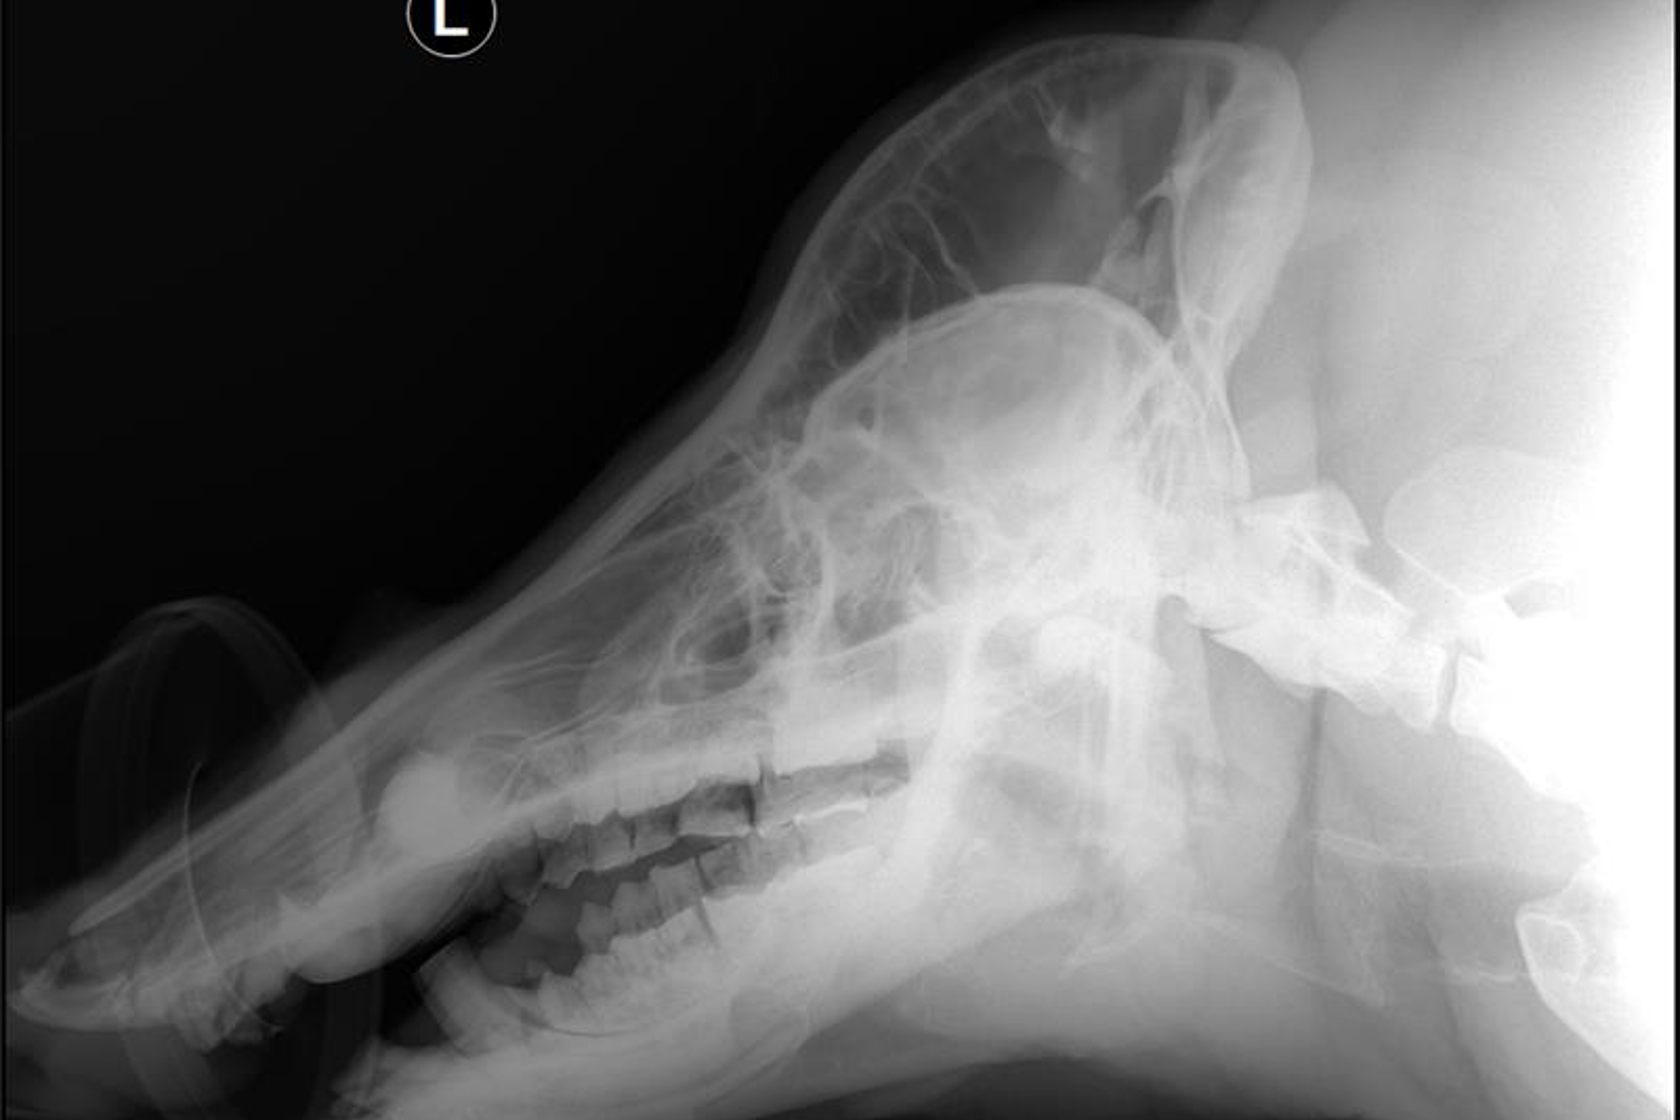

Once at the vets we carried out a full body MOT on Tre. This involved bloods, x-rays, an ear check, hoof check, coat check, as well as teeth check and polish.